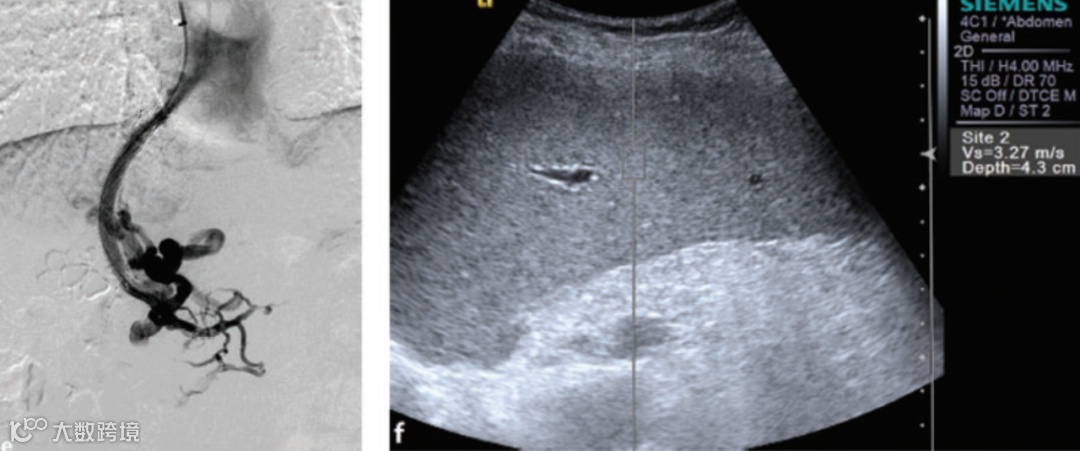

Han H, Yang J, Jin WK, et al. Diagnostic value of conventional ultrasound and shear wave elastography in detecting transjugular intrahepatic portosystemic shunt dysfunction. Acta Radiol 2020

经颈静脉肝内门体分流(TIPS)功能障碍可导致门静脉高压(PH)相关的并发症,如腹水和胃食管静脉曲张破裂出血。而侵入性门静脉造影价格昂贵,限制了其作为筛查手段的使用。近日,来自我国南京鼓楼医院的Han H等人评估了常规超声结合点剪切波弹性成像(pSWE)在预测TIPS功能障碍中的临床价值,相关内容发表在Acta Radiologica杂志上。

该回顾性研究分析了184例行TIPS的肝硬化患者。测量患者的脾门静脉血流参数,肝硬度(LS)和脾硬度(SS)。测量结果包括门静脉速度(PVV)、脾静脉速度(SPVV)、LS和SS的差异。探讨PVV(ΔPVV)、SPVV(ΔSPVV)和SS(ΔSS)变化对诊断TIPS功能障碍的准确性。

结果显示,184例患者中有28例出现TIPS功能障碍(15.2%)。18例(64.3%)有分流性狭窄,10例(35.7%)有分流阻塞。TIPS正常和TIPS功能障碍组之间的门静脉直径(PVD)、PVV、脾静脉直径(SPVD)、SPVV、LS和SS没有显著差异。与TIPS正常组相比,TIPS功能障碍组患者的PVV和SPVV显著降低,而SS明显升高(P<0.001)。ΔPVV、ΔSPVV和ΔSPV的受试者工作特性曲线下面积分别为0.97、0.96和0.87。

因此,pSWE对TIPS功能障碍的诊断效果与常规方法相当,可在TIPS术后常规应用。